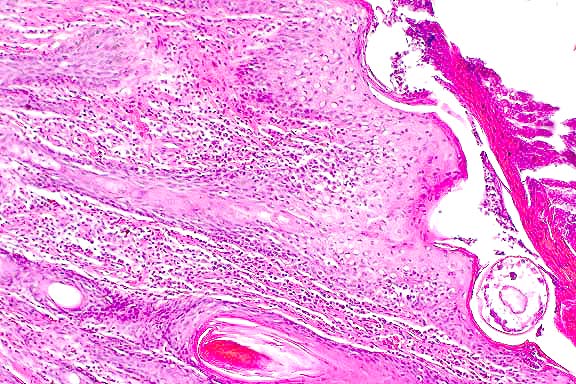

- Case 13-1. Skin. Numerous hair follicle-like structures

expand the dermis.

- AFIP Diagnosis: Haired skin: Benign hair follicle

tumor, with few intranuclear inclusion bodies, golden Syrian

hamster (Mesocricetus auratus), rodent.

- Conference Note: An unencapsulated, well-circumscribed,

multilobulated neoplasm expands the dermis and subcutis, and

compresses subjacent skeletal muscle. The neoplasm is composed

of lobules of epithelial cells arranged in nests, broad cords

and hair follicle-like structures. A peripheral layer of basophilic

polygonal cells aligns along the basement membrane, and neoplastic

cells are more eosinophilic within inner layers of the abortive

hair follicles. Small numbers of intranuclear inclusions are

within the more mature, inner layers of neoplastic follicular

epithelium.